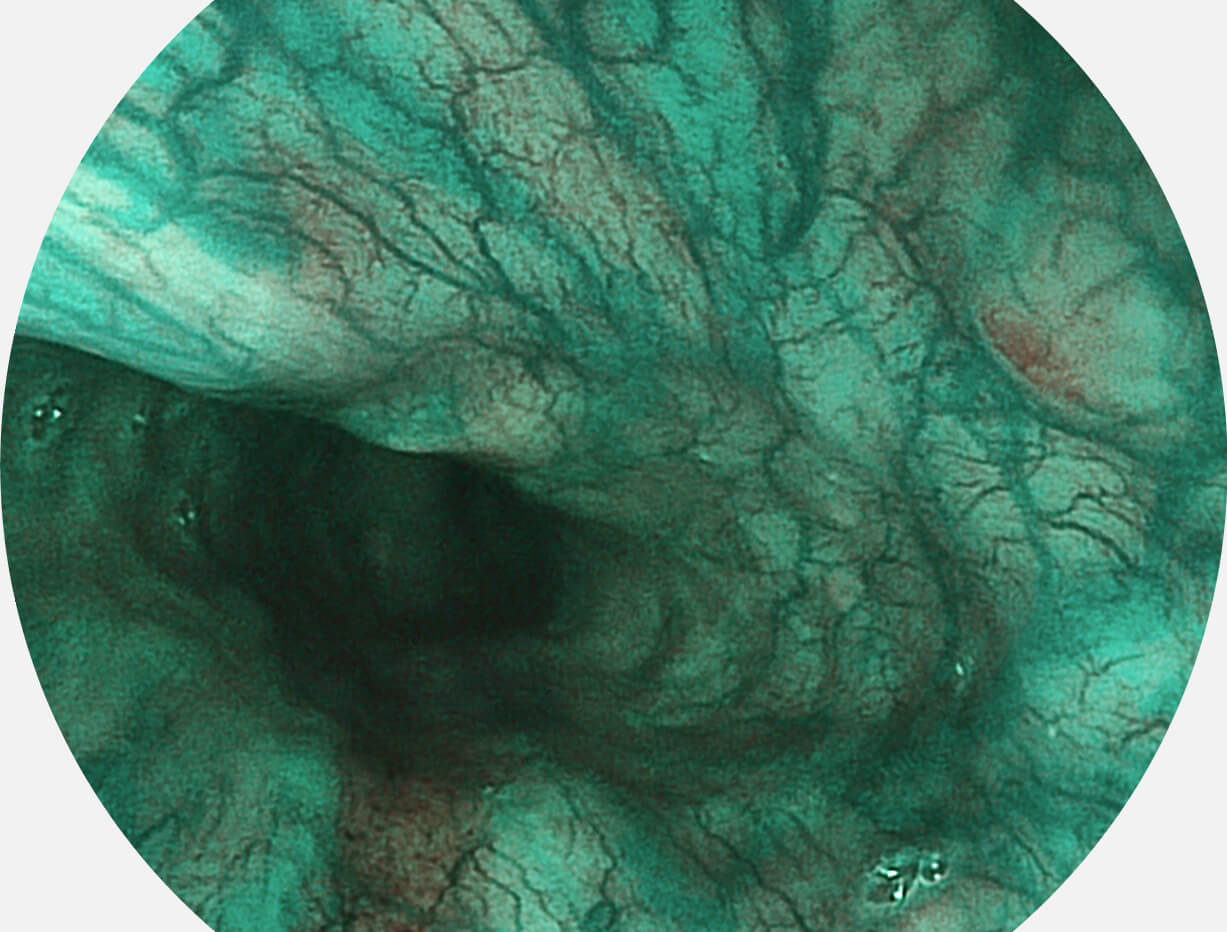

SFI图像

Versatile Intelligent Staining Technology, VIST

强调浅层黏膜结构的同时,保证照明亮度和提升浅层微血管与中层血管颜色对比度,病变边界更清晰。

白光图像

VIST图像

采用光路合束技术,光谱自由度高,实现了更丰富的照明模式,染色模式SFI及VIST,从远景到近景,助力消化道早期疾病诊断。